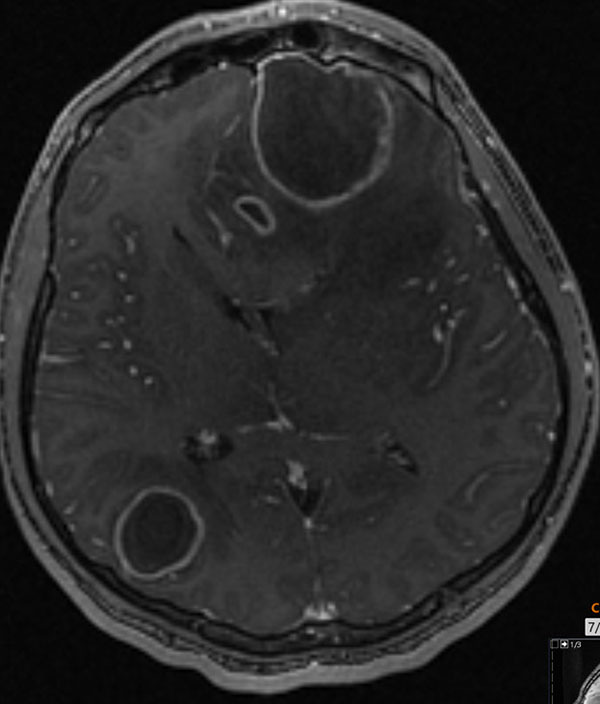

Symptoms typically have an indolent onset, starting with low fevers and headache, and progressing to vomiting and neurologic changes. A head CT or magnetic resonance imaging (MRI) of the brain allows for an accurate diagnosis. See Figures 9 A-B for a brain MRI that depicts the typical findings of abscesses secondary to Streptococcus. Figures 10 A-C show a classic epidural abscess. Given the possibility of elevated intracranial pressure, lumbar puncture should be avoided because of the risk of herniation.

Figure 9A. Brain Magnetic Resonance Imaging Enhancement of Abscesses |

![]() |

Brain magnetic resonance imaging post-contrast T1 depicting rim enhancement of abscesses Used with permission from Sean Kelleher, MD, Dayton Children’s Hospital. |

Figure 9B. Brain Magnetic Resonance Imaging with Fluid and Edema |

Brain magnetic resonance imaging T2 showing complex fluid within the lesion and extensive adjacent edemas Used with permission from Sean Kelleher, MD, Dayton Children’s Hospital. |